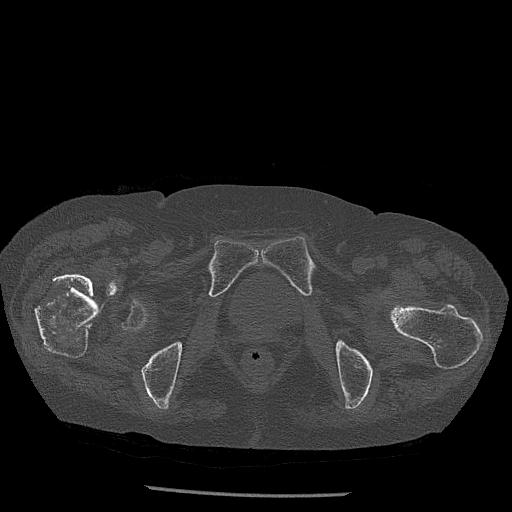

100703 1/27 両股正面+軸 1/29 両股正面+軸 94歳女性 パンソンロン